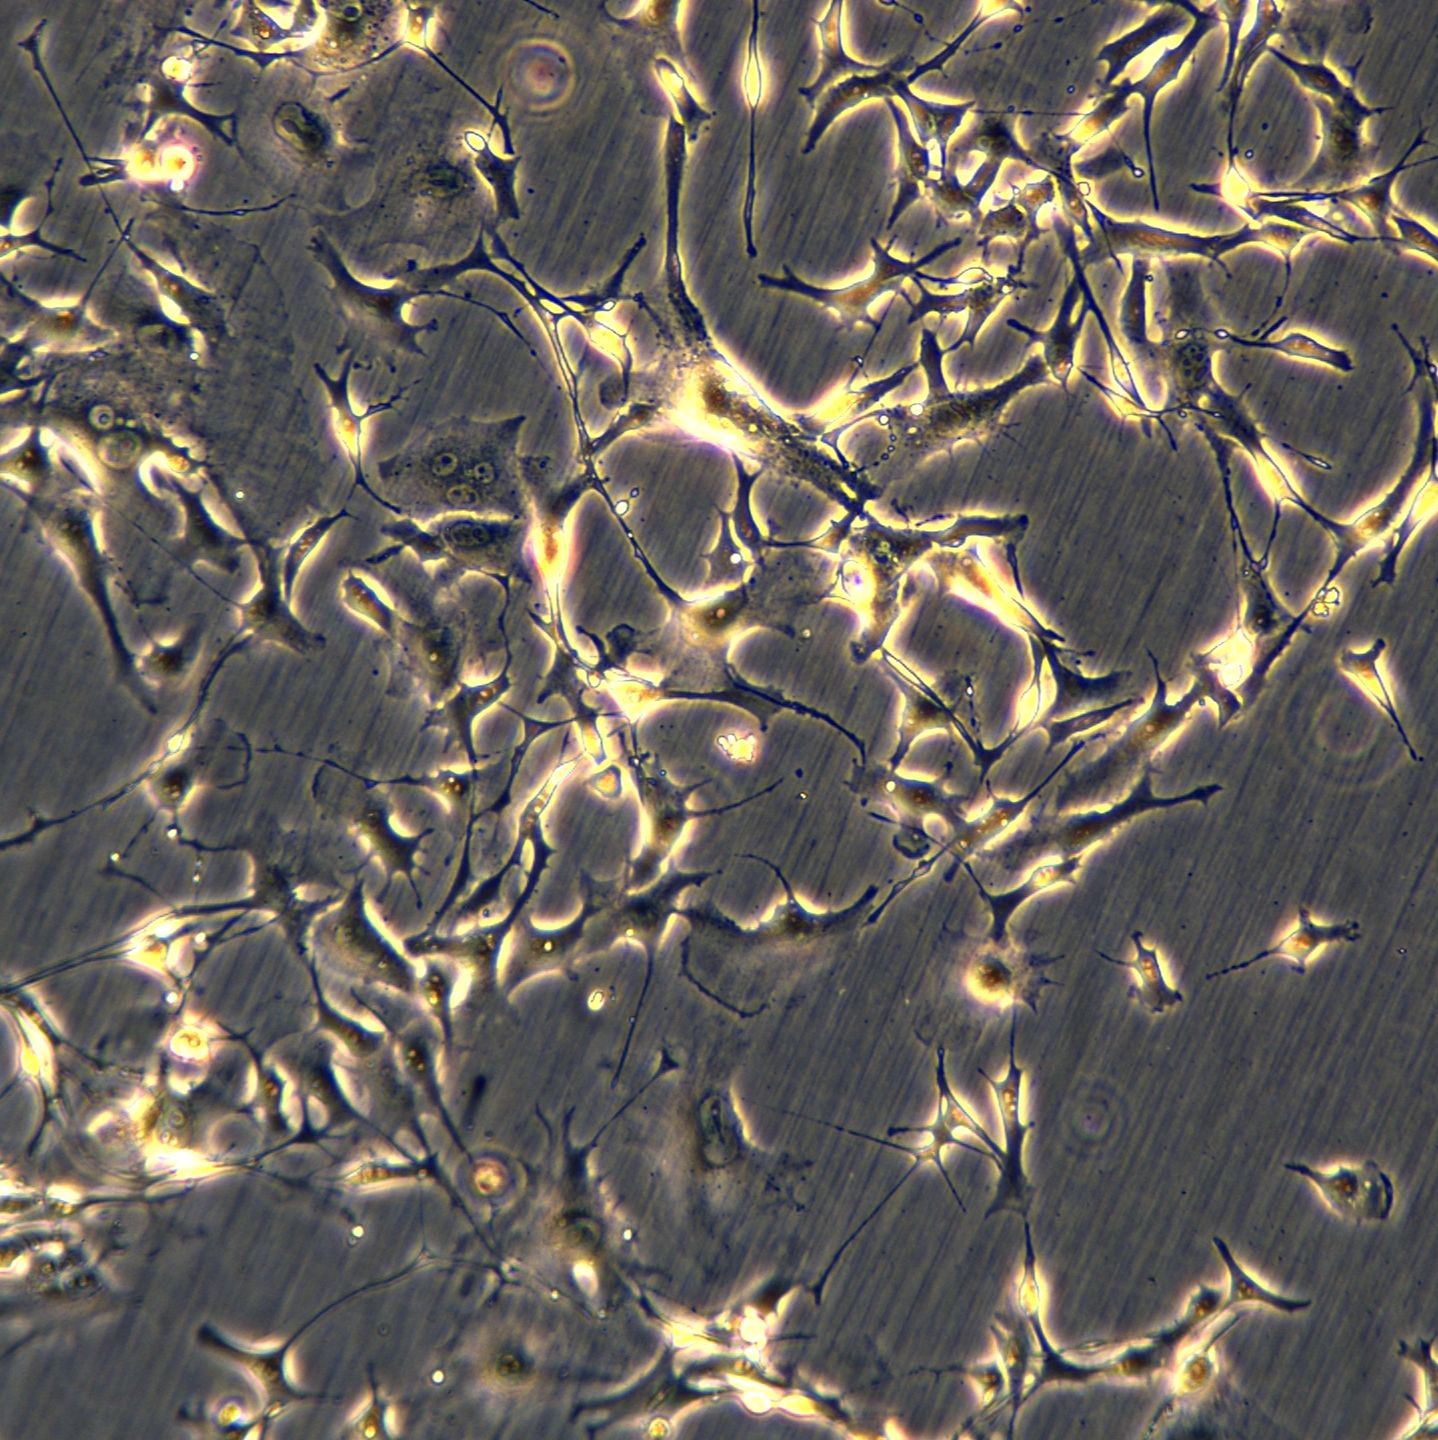

表皮样细胞(Epithelial-like)

贴壁生长(Adherent)

B16-OVA是小鼠黑色素瘤细胞系B16-F10经过基因工程改造后建立的细胞模型,其核心特征是稳定表达模型抗原鸡卵清白蛋白(OVA)。该细胞保留了亲本B16细胞的高度恶性、高增殖和转移特性,同时能够持续将OVA肽段呈递给其MHC I类分子(H-2Kb)。

B16鼠黑色素瘤细胞。好像这株细胞还有亚型的,不过中科院说不清,我也就说不清了。总之是B16。细胞总的来说比较好养,操作基本都是常规的。要求用胎牛10%1640、5%CO2、37度培养,一段时间为了省钱用过新生牛也不错。但是传代多了,细胞有形态改变。可以弃掉重新复苏。血清国产的杭州四季青,感觉不灭活比灭活要好养一些。传代操作,主要是无菌操作。细胞增殖快非常好养,但是及时换液,否则也很容易死亡、或变形。消化用胰酶0.25%,可以用含EDTA的,效率更高一点。消化步骤:弃血清——用D-hank's